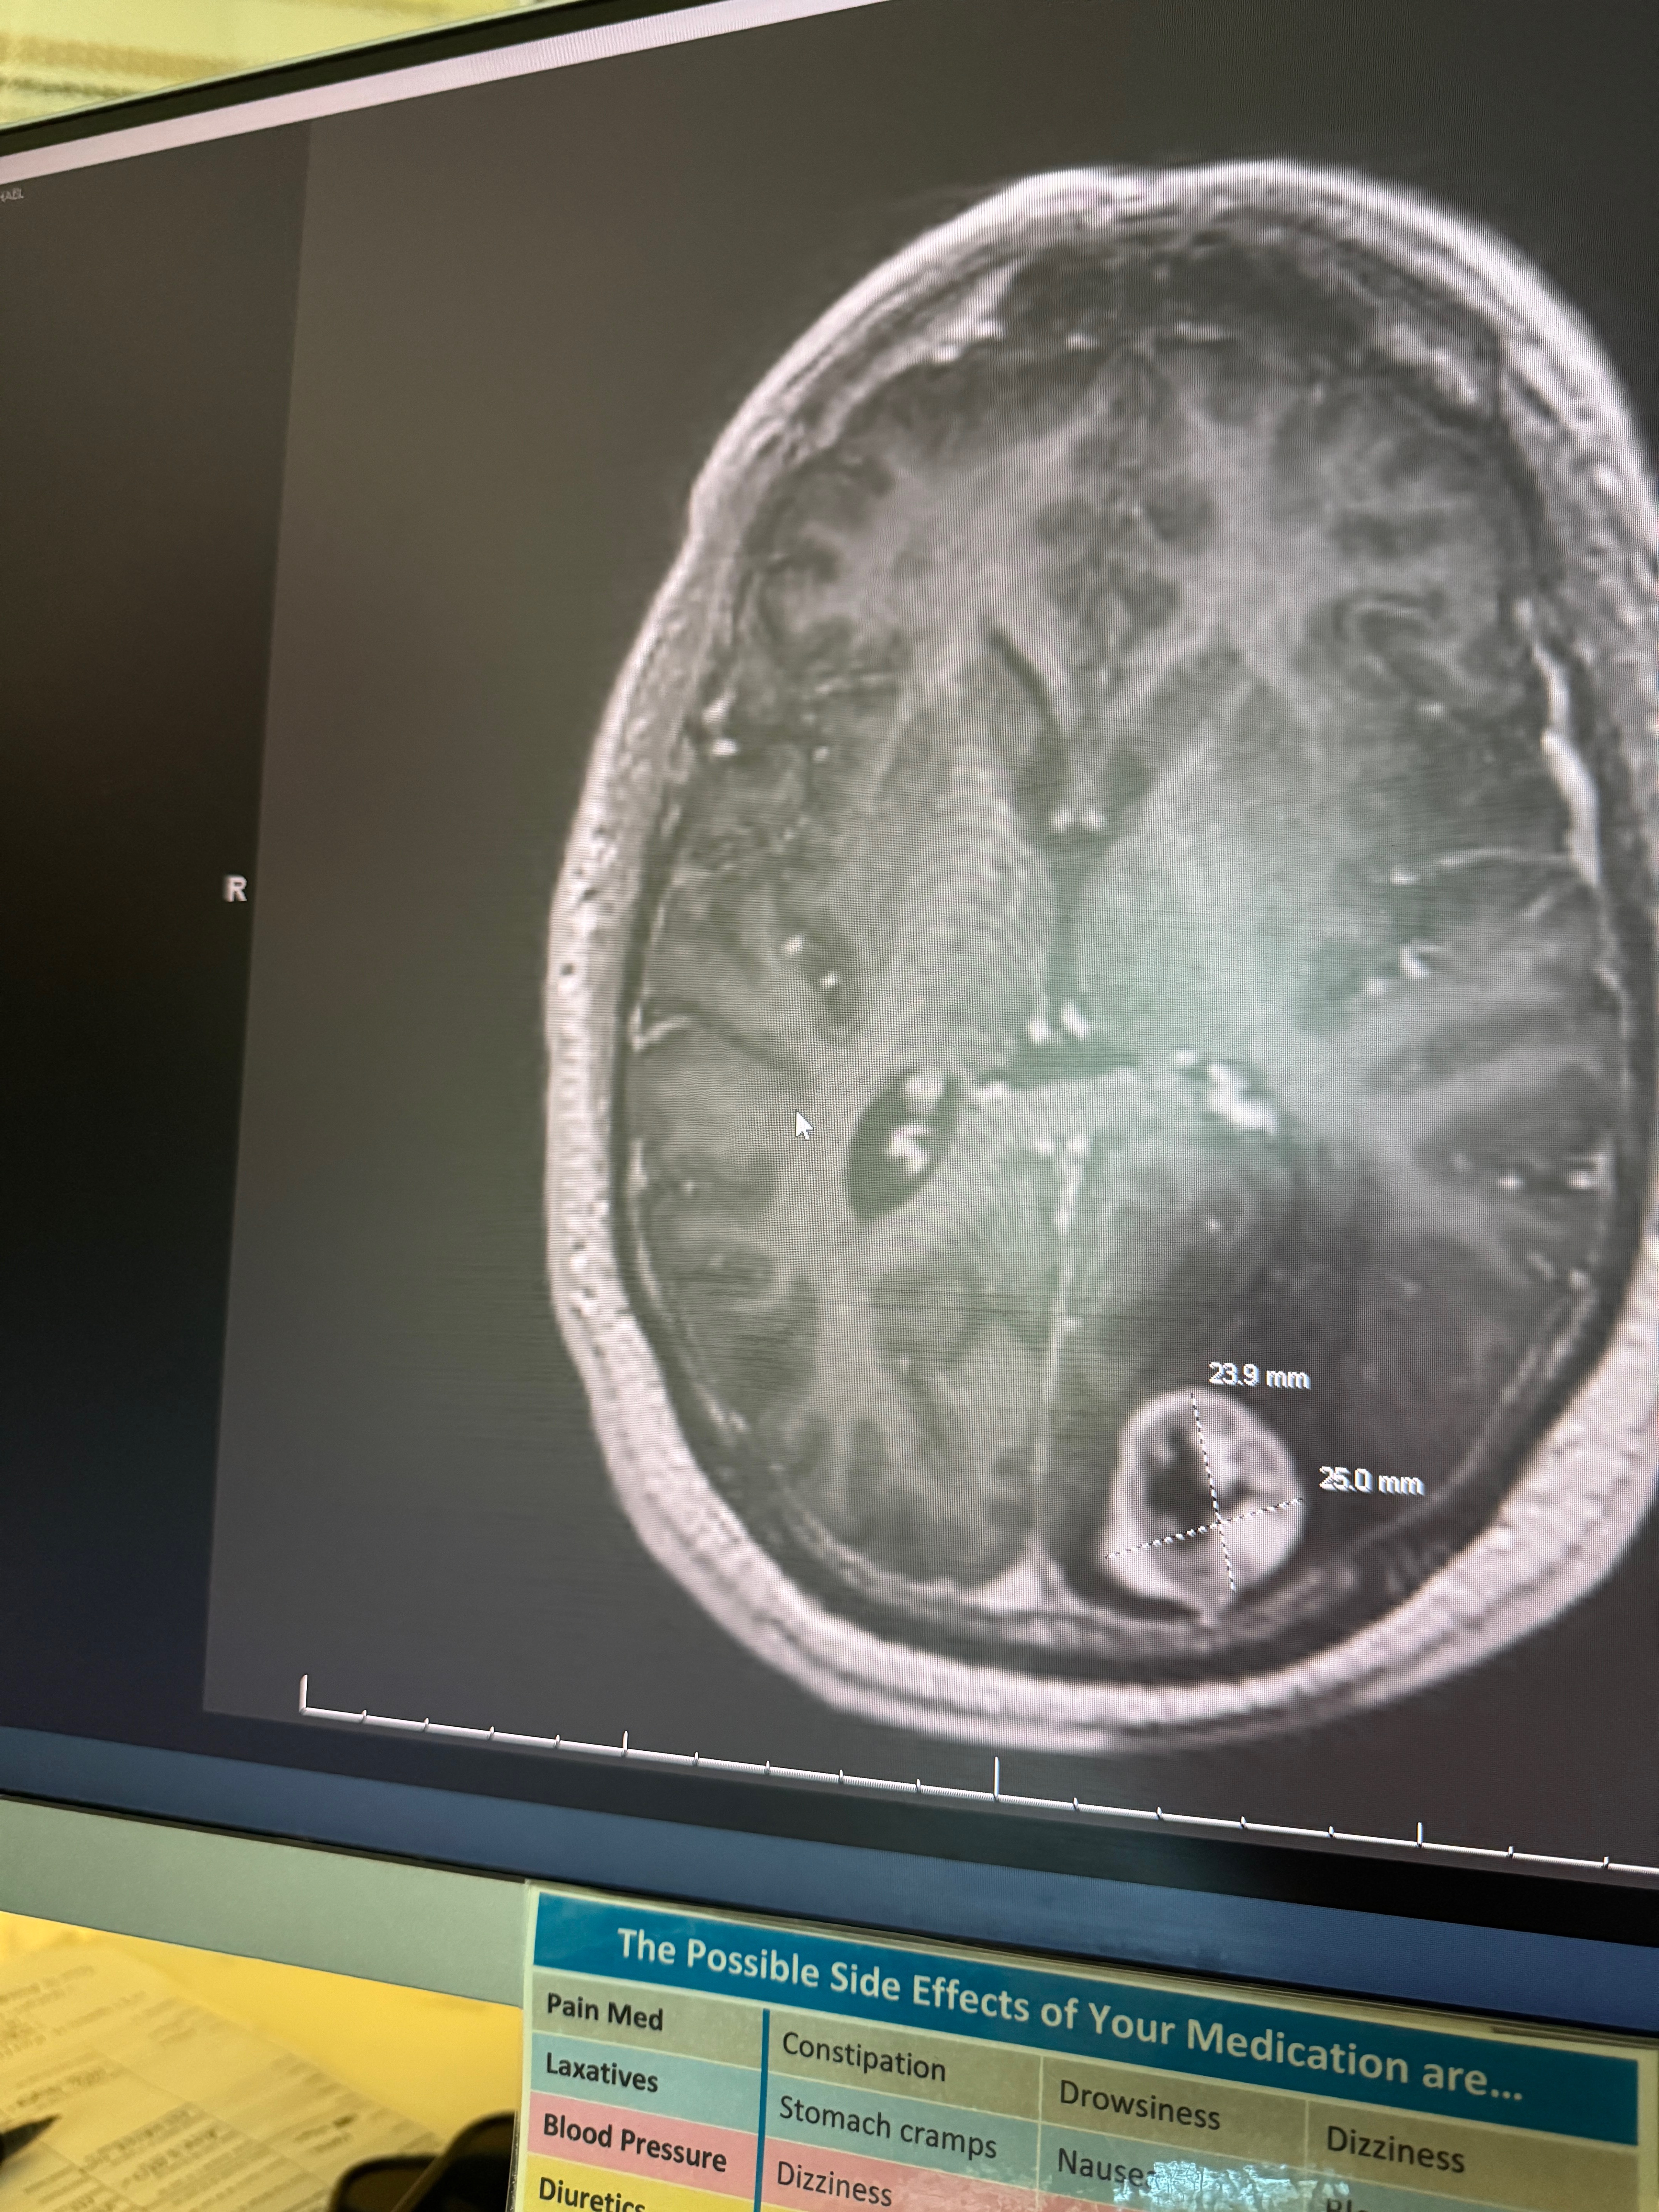

As many of you already know on August 18th, I was diagnosed with a highly aggressive and advanced form of brain cancer. After complaints of confusion and aphasia an MRI revealed multiple tumors, some quite large throughout my brain, and there was massive swelling. My blood sugars were way too high. My doctor sent me to the emergency room, where they told me the terrible new and admitted me immediately.

While I was in the hospital, further testing revealed that my cancer most likely began in my kidneys, a renal carcinoma. From there it moved into my lymph nodes and it is present in my femur bones and in both lungs, the neck and throughout the head. Additionally, a skin cancer has developed on my right-hand index finger, under the fingernail which will result in a partial amputation of the finger. To be clear, my condition is terminal.

On September 15th my treatments began. They sent targeted radiation directly to the brain tumors, and I received my first chemotherapy infusion. In the days that followed my mind and body deteriorated into disability levels. I had extreme confusion and fatigue, painful mouth sores and swelling of my feet and legs. My recovery time has been more than 10 days to get to this point and I am still not 100% This was round one of ten. Nine more chemo infusions, the next one will be this Friday October 10th. I expect next week, and all the weeks following these treatments will be difficult.